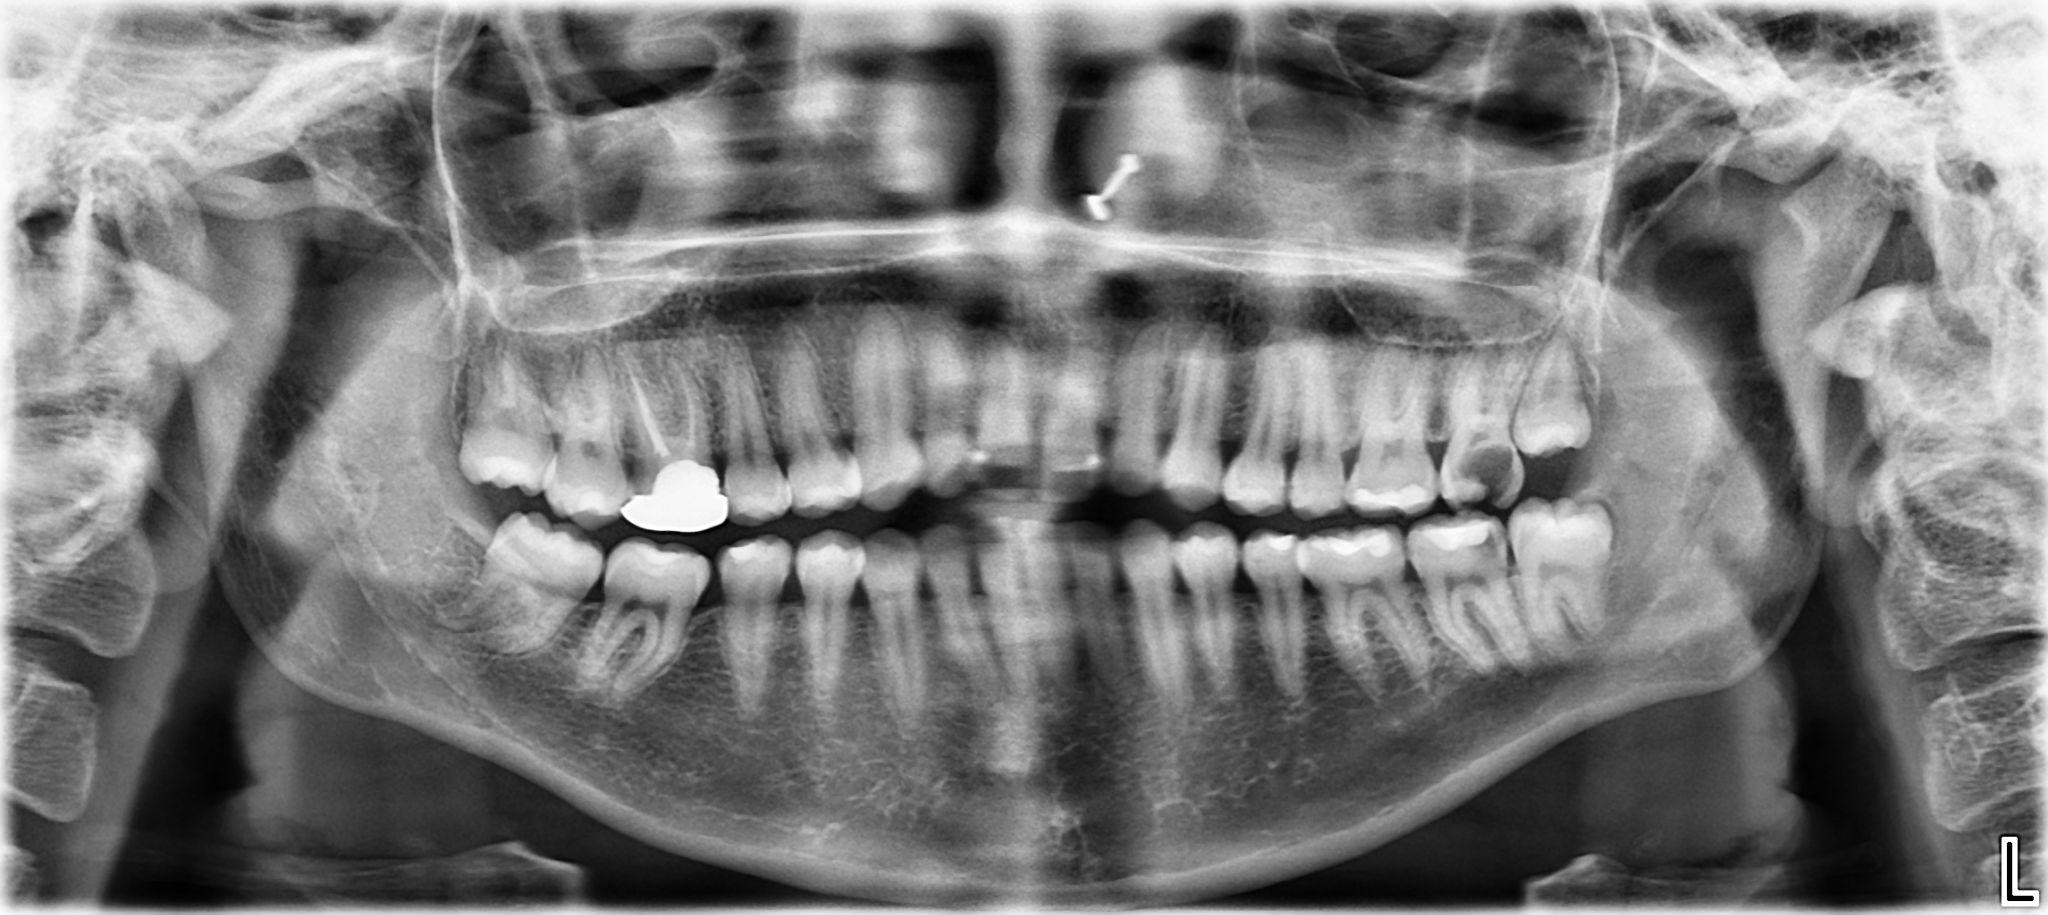

9. What options can be selected for the first quadrant of this panoramic X ray?

10. What options can be selected for the second quadrant of this panoramic X ray?

11. What options can be selected for the third quadrant of this panoramic X ray?

12. What options can be selected for the forth quadrant of this panoramic X ray?